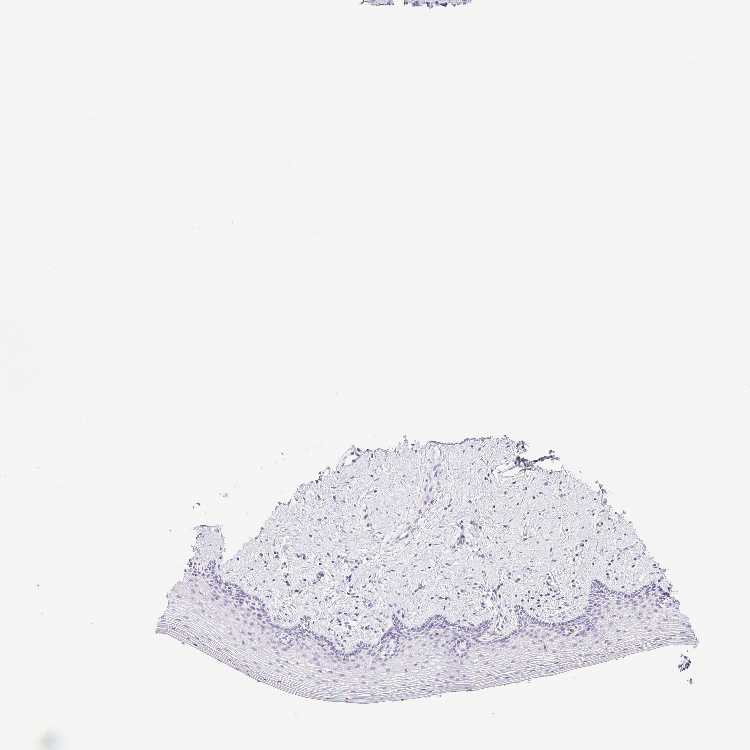

VAGINA - Antibody stainingi

Antibody staining in the annotated cell types in the current human tissue is reported as not detected, low, medium, or high, based on conventional immunohistochemistry profiling in selected tissues. This score is based on the combination of the staining intensity and fraction of stained cells.

Each image is clickable and will lead to virtual microscopy that enables deeper exploration of all samples and also displays staining intensity scores, fraction scores and subcellular localization as well as patient and tissue information for each sample.

Antibody HPA018412Antibody HPA018430

Squamous epithelial cells Not detectedNot detected